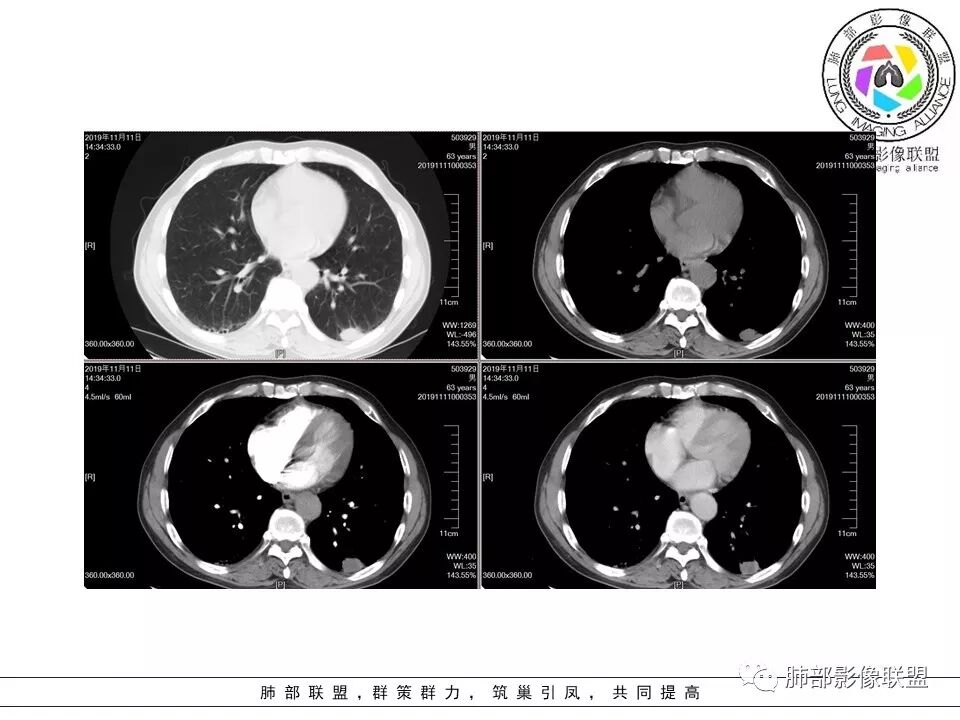

病理结果:巨细胞癌。

1.临床特征:发生率极低,约占所有肺部肿瘤 0.3%-0.4% ,多数患者有大量吸烟病史。

转移特点:常转移至骨、肾上腺、肺、肝和肾,较易转移至小肠特别是空肠,可引起梗阻、肠出血甚至肠套叠。

2.影像特征:周围型多见,中央型不足30%。较大的周围型肿块,易大范围坏死,囊样变甚至空洞形成。增强扫描常见环形强化。肿瘤多发生在肺上叶。PET-CT:肿瘤因高代谢而致SUV值较高。

3. 病理特点:肉眼见恶性肿瘤的切割面通常是灰白色或黄褐色,并经常出现黏液、坏死和/或出血灶,在CT增强扫描上这些区域往往表现为低密度。

4. 发病和遗传学改变:c-myc扩增,部分有K-ras 突变。

5. 预后:因生长迅速侵袭性强,预后很差,5年生存率约为10%。